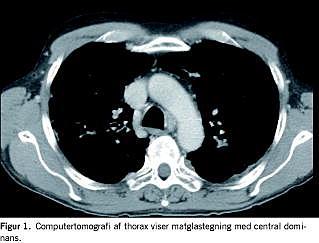

I. En 59-årig mand, der havde haft rektosigmoiditis siden 1981, fik opblussen under vedligeholdelsesbehandling med azathioprin og mesalazin. Behandling med højdosis steroid kompliceredes af aseptisk knoglenekrose og måtte seponeres. Patienten ønskede ikke operation, og derfor påbegyndtes behandling med infliximab med god effekt på hans tarmsymptomer. Der forelå negativ interferon-γ-test for tuberkulose (TB). Efter anden kur blev han træt og fik dyspnø, hovedpine, høj feber og forhøjet C-reaktivt protein. En røntgenundersøgelse af thorax viste et lille infiltrat. Luftvejssekret blev undersøgt for almindelige luftvejspatogener, legionella, pneumocyster samt TB og blod blev undersøgt med Cytomegalovirus (CMV)-polymerasekædereaktion (PCR) og Aspergillus galactomannan-antigentest. Patienten påbegyndte behandling med penicillin og clarithromycin uden effekt. På grund af tiltagende luftvejssymptomer og hypoksi med saturationsfald til 80% under korte gåture skiftede han til peroral sulfamethoxazol/trimethoprim og samtidig steroidkur. En computertomografi af thorax viste matglastegning (Figur 1). I trakealsekret og bronkial alveolær lavage fandt man ved PCR-undersøgelse P. jiroveci. Alle øvrige mikrobiologiske undersøgelser var negative. Patienten responderede godt på sulfamethoxazol/trimethoprim. Han fik dog pancytopeni i slutningen af kuren, hvorfor sulfamethoxazol/trimethoprim blev midlertidigt pauseret med god effekt. Patienten blev efterfølgende kolektomeret, og immunsuppressiv behandling kunne seponeres. Tre måneder senere afsluttedes den profylaktiske sulfamethoxazol/trimethoprimbehandling.

Taksigelse: Rene Jensen og Stanislaw Wasilewski, Billeddiagnostisk Afdeling, Regionshospitalet Viborg, takkes for hjælp til Figur 1.